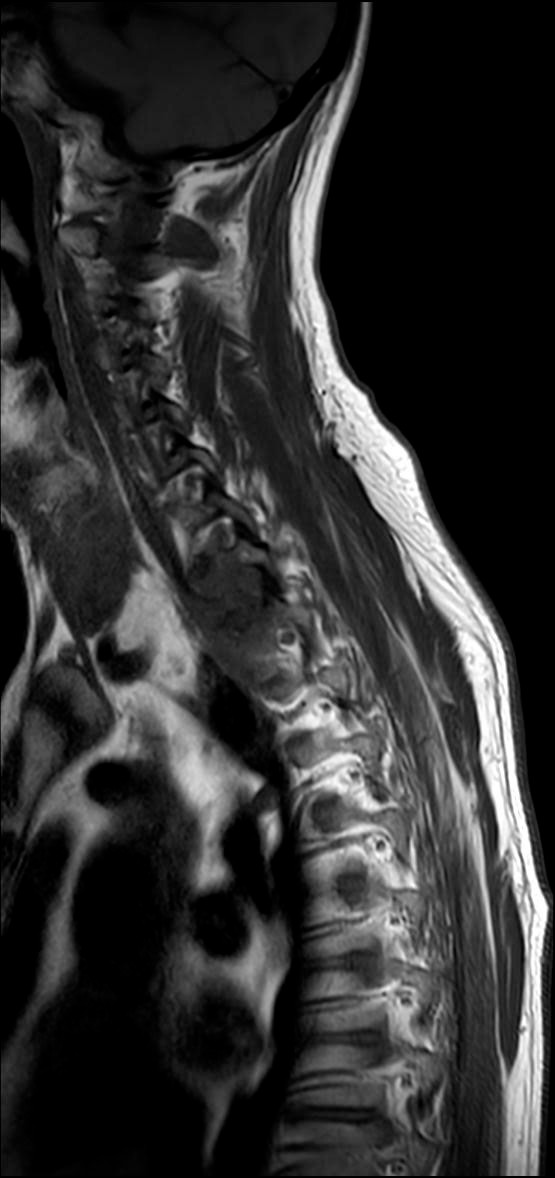

MR av hals og øvre del av thorax ble gjennomført og viste en stor tumor på 4,8 × 2,8 cm i høyre lungeapex. Prednisolon ble seponert, og pasienten ble henvist til CT og MR som bekreftet en tumor apikalt i høyre overlapp (figur 1) med gjennomvekst til costae I og II, corpus vertebrae Th1 og nevroforamina med påvirkning av C8- og Th1-røtter og plexus brachialis (figur 2), innvekst i a. subclavia og metastasesuspekte lesjoner i virvlene C7, Th5, L1, L3 og L4. CT abdomen viste ingen sikre metastaser. Pasienten ble overflyttet til lungemedisinsk avdeling for videre utredning på grunn av mistanke om primær lungekreft.

Selv om det ikke ble funnet noen atypiske celler i biopsimaterialet og behandling med vorikonazol ble iverksatt, kunne man fremdeles ikke avfeie kreftmistanken. Bildene ble regransket av radiolog, og funnene var fortsatt best forenlig med malignitet, ikke med soppinfeksjon. Dessuten var det flere metastasesuspekte lesjoner i ryggvirvlene (figur 4). Det ble derfor tatt nye biopsier fra en av lesjonene i ryggsøylen. De nye biopsiene, med en rekke immunhistokjemiske analyser, bekreftet at det dreide seg om spredning fra udifferensiert ikke-småcellet lungekreft.

Kreftcellene hos vår pasient hadde høyt uttrykk av programmert celledød-ligand 1 (PD-L1)-proteiner, og han ble vurdert til å være kandidat for immunterapi etter strålebehandling. Strålebehandlingen ble startet omtrent to uker etter avklaring med biopsier, og han fikk 3 Gy × 13 mot primærtumor, dette i håp om å redusere smertene og de nevrologiske symptomene. En ny CT-undersøkelse i forbindelse med strålebehandlingen viste betydelig progrediering av primærtumor og tilkomst av nye metastaser i lever, høyre binyre og flere lymfeknuter samt betydelig økning av metastaser i columna uten kompresjon av ryggmargen. Det ble dessuten påvist lungeembolier bilateralt, som ble behandlet med lavmolekylært heparin. Han kom i gang med strålebehandling mot metastaser i L1–L4-området, og rakk å få 4 Gy × 4. En akutt tarmperforasjon oppsto, og pasienten ble laparotomert med reseksjon og anleggelse av sigmoidostomi. Han fikk piperacillin/tazobaktam intravenøst. Tarmperforasjonen ble komplisert, med abscessdanning og raskt utviklende sepsis. Pasienten døde av multiorgansvikt på grunn av alvorlig infeksjon og raskt progredierende kreftsykdom omtrent tre uker etter gjennomført strålebehandling og tre måneder etter første innleggelse.